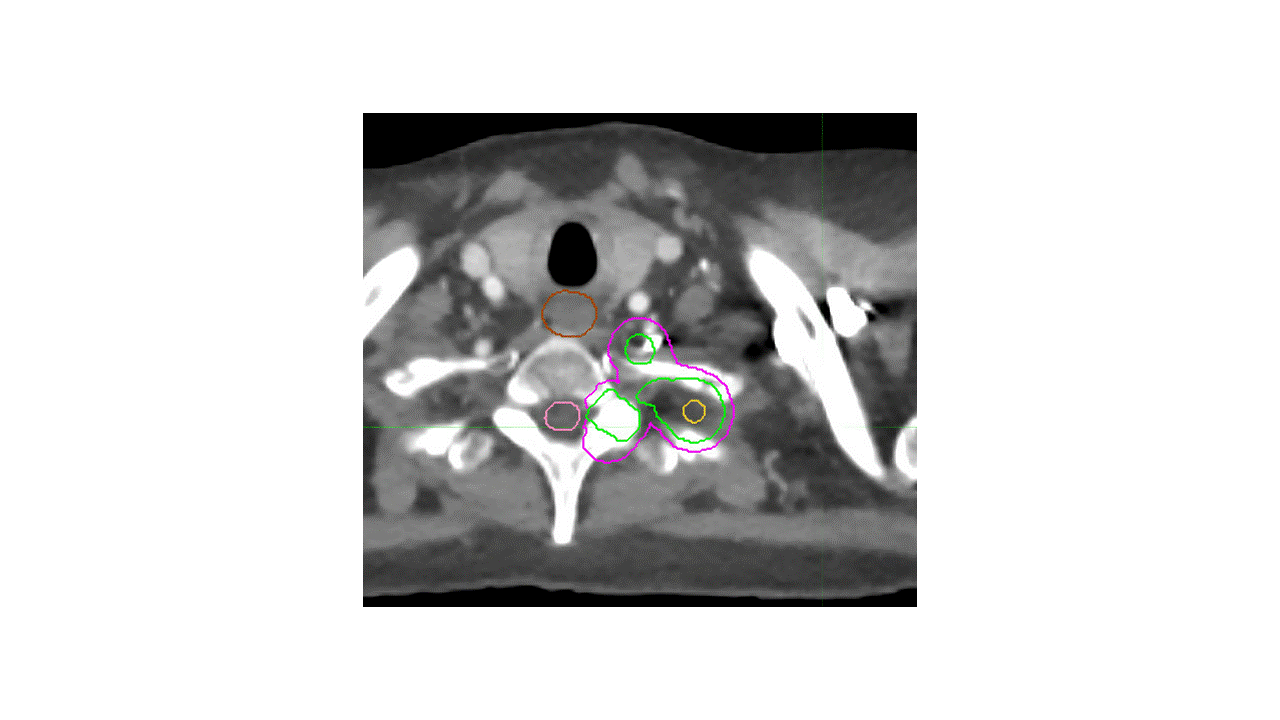

Ways to Contour

Alternative 1

Alternative 2

Which volumes are the most appropriate?

A. LUL primary tumor with margin, no LN and limited vertebral body inclusion

B. LUL primary tumor + hilar LN, with inclusion of entire vertebral body and left-sided pedicle/process/lamina

C. LUL primary tumor and limited vertebral body inclusion + hilar/mediastinal lymphadenopathy

Answer: B

There are several potential approaches to this case. Given that the mass extends into the vertebral body and the T2 neural foramen, with unclear borders, the International Spine Radiosurgery Consortium consensus guidelines were utilized, with inclusion of the ipsilateral neural foramen and vertebral body substructures. Choices A and C are too limited with respect to vertebral body coverage, and actually appear to miss gross disease. A thin-slice MRI scan was used for treatment planning and a spinal cord PRV was utilized to ensure appropriate coverage with adequate sparing of the spinal cord.

The second major question is whether to cover the left hilum and the mediastinum. Given that the EBUS was negative, it would be reasonable to omit the entire mediastinum. However, in this case, the decision was made to cover the ipsilateral hilum given the strong avidity in the left hilum and the proximity of the mass to the left hilum, this region was covered as well.